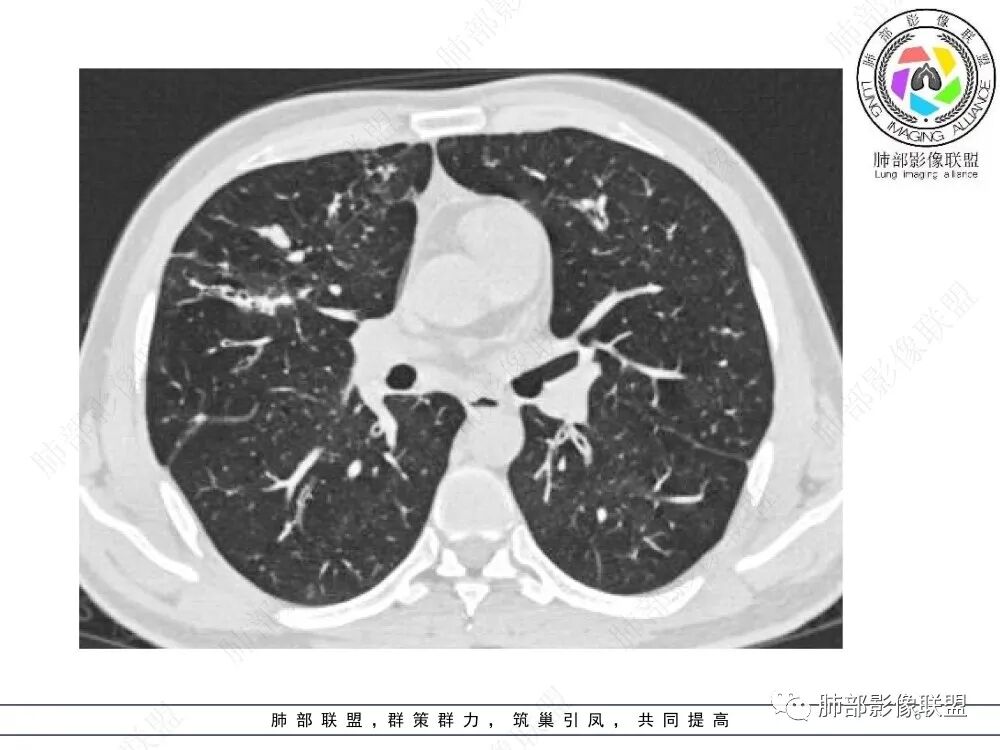

肺部影像联盟晨读病例肺气肿,多发气管壁增厚,片状影,符合气道分布,考虑气道侵袭性曲霉菌病。

中年男性,慢性咳嗽,有吸烟史,胸部CT基础尚可,双肺多发的沿支气管播散的树芽影以及支气管管壁的增厚和对应区域内的斑片影实变影,符合气道播散的表现。经过对症抗感染治疗1月之后,胸部CT影像进展。右侧播散到左侧。实变和漱牙以及气管壁增厚均较前明显进展。

两肺多发弥漫性腺泡结节,支气管壁增厚,抗炎治疗后病变范围较前进展,沿支气管血管束分布,两肺见多发树芽及增厚扩张支气管,以右中叶及左上叶舌段为著,年轻患者,慢性病史,扩张支气管周围肺野未见肉芽肿性病变,抗炎治疗无效可排除诺卡及铜绿感染,综合分析首选NTM,其次气道侵袭性曲霉。

两肺支气管壁增厚,散在斑片状及树芽状影,抗炎治疗后病变范围进展,沿支气管血管束分布,两肺多发结节、树芽、实变及囊腔影,年轻患者,慢性病史,肺气肿背景,考虑气道侵袭性曲霉,鉴别NTM+铜绿。

两肺广泛支气管轻度扩张及管壁增厚,厚薄稍不均,累及叶段支气管,周围见散在斑片状密度增高性,部分实变,边缘模糊,下叶为著。考虑炎症,首先气道侵袭性曲霉,ntm待排。

晨读:最关键的有三点:1、临床表现及病史:35岁,男性,慢性刺激性咳嗽2月,吸烟史17年,没有糖尿病和其他免疫缺陷病史。这儿应该隐瞒了关键的吸入环节,存在大量曲霉孢子的工作环境没给。2、第一次影像改变:广泛的支扩,支气管壁增厚,多发的树芽,部分区域已经伴有支气管周围的渗出,少量实变。3、20多天后复查的影像,原有支扩,支气管壁增厚基础上的大量渗出,实变,伴结节,胸膜下累及。

2.胸部CT:两肺广泛的支扩,支气管壁增厚,多发的树芽影,部分伴有支气管周围的渗出,少量实变。不足一月复查,原有支扩、支气管壁增厚基础上伴有大量渗出,实变,结节,胸膜下累及。